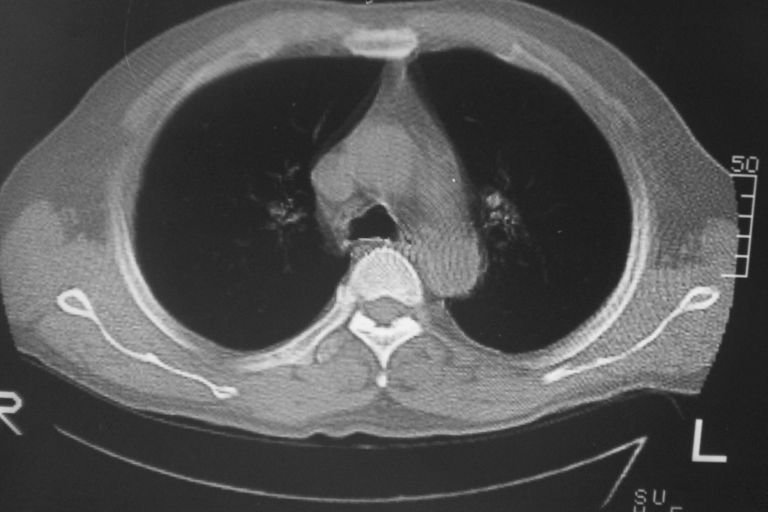

标题: CT10574:男 50岁胸部CT请会诊!

患者 男 50岁 无痛性咯血3天,无其他不适.

1 左肺下叶基底段见两结节软组织密度灶抗炎后复查

2心包积液

1 左肺下叶后基底段见结节软组织密度灶,建议抗炎后复查,排除肿瘤

1、左肺下叶两个结节影,建议抗炎治疗后复查.

2、心包积液

左下肺结节状软组织密度影,一个边缘有卫星病灶,邻近胸膜增厚.另一个有毛刺.心影周围水样密度影环绕.考虑:

1.肺癌可能.肺tb待排.

2.左侧胸膜增厚.心包积液.